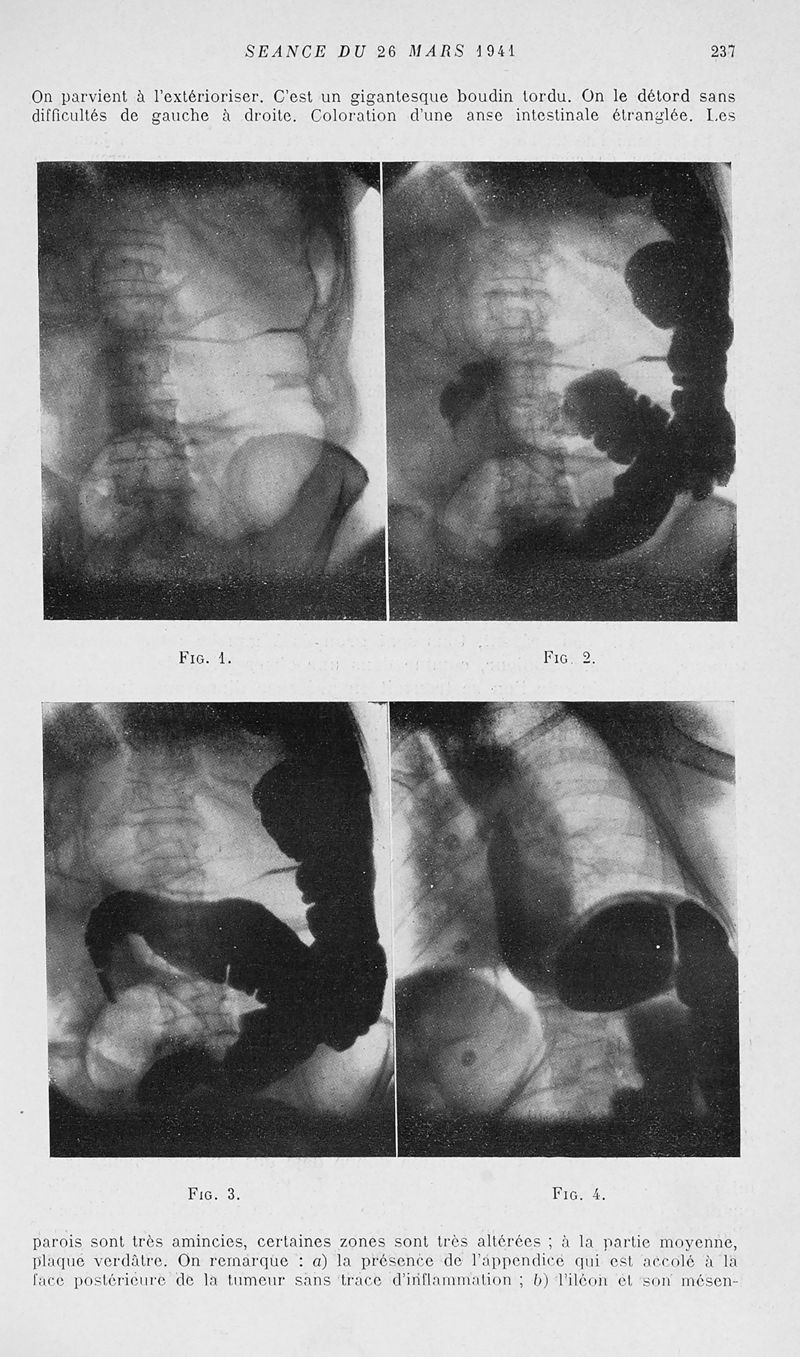

Mémoires de l'académie de chirurgie

Tome 67, 1941. - Paris : Masson, 1941.